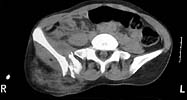

A woman in her 30's in a high speed MVC with this closed pelvic fracture. She's hemodynamically stable, no other injuries - belly, chest, and head are all fine. She also has a comminuted supracondylar femur fracture on the R side.

Preop AP

Preop CT